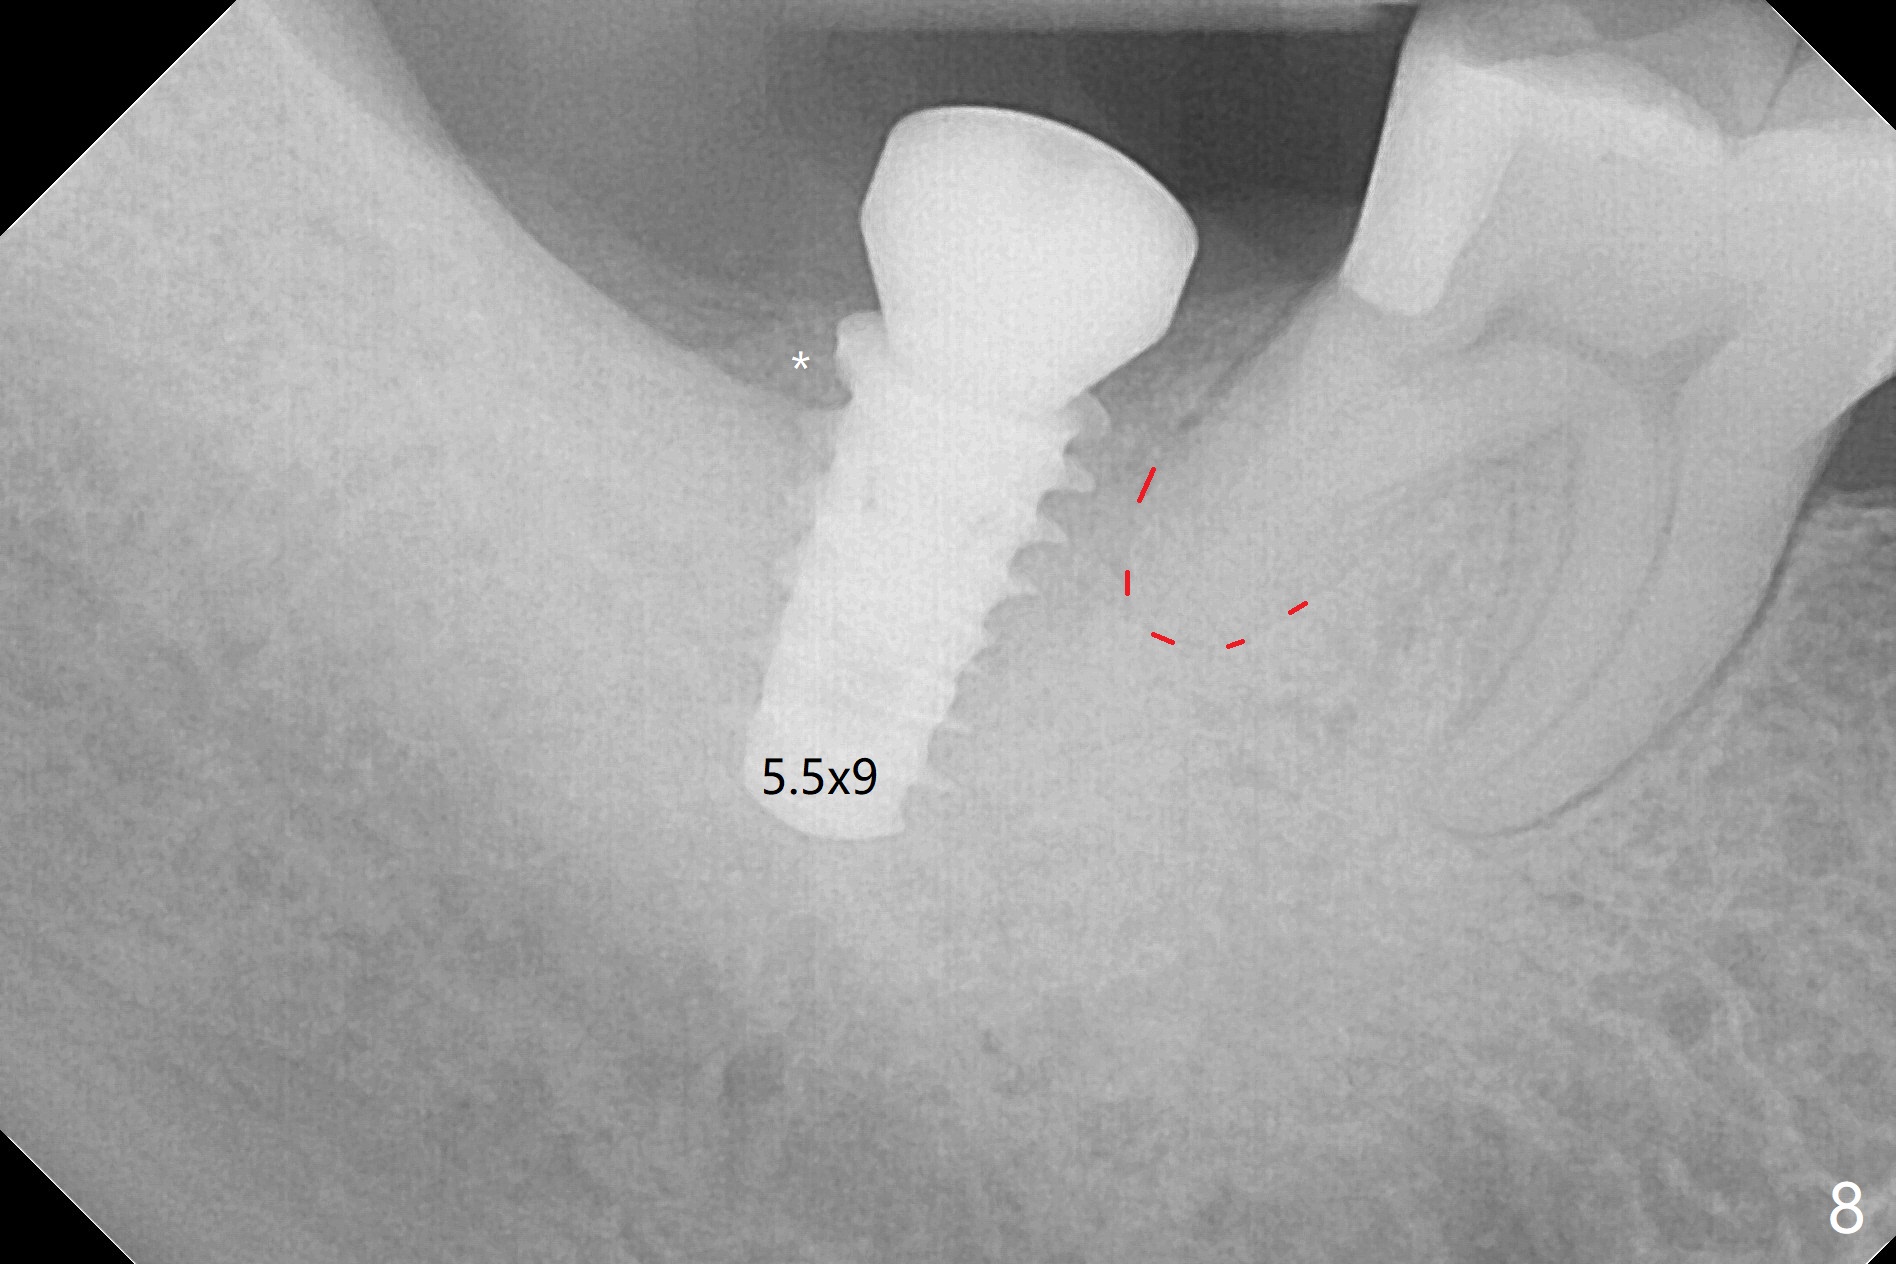

The socket shrinks with buccal plate reduction 3 months post socket preservation (Fig.5), as compared to 10 days postop (Fig.4). To restore the socket as much as possible, Magic Split is used (flapless), followed by Magic Expanders 3-3.8 mm for 11 mm (gingival level) and a 4x11mm dummy implant (Fig.6). The osteotomy is moved distal by using Lindamann bur; following 3.8 mm Magic Drill, a 4.5x11 mm dummy implant (Fig.7). Finally a definitive 5.5x9 mm implant is placed with <45 Ncm; a 6x2 mm healing abutment is placed to close the access (Fig.8). Autogenous bone harvested from the Magic Drill returns to the osteotomy mainly buccal prior to implant placement (Fig.8 *). The patient reports no discomfort immediately postop, thanks to the flapless technique. The patient has had postop pain; 11 days postop, the abutment and implant are found to be loose. After re-tightening by hand, the complex is seated deeper and more stable (Fig.9 arrow).